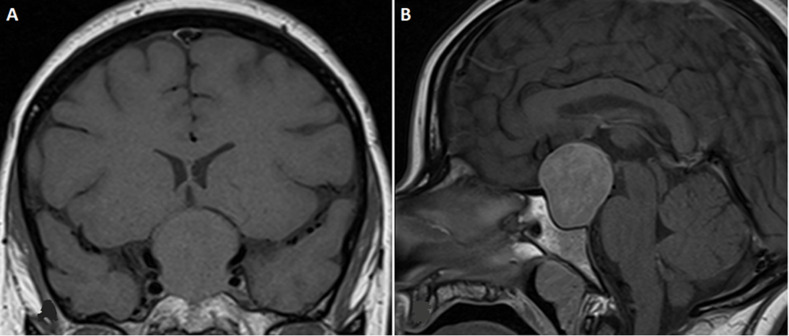

We report the case of a functional gonadotropic adenoma (FGA) in a 32-year-old woman, initially revealed by ovarian hyperstimulation. Hormonal investigations strongly suggested an FGA; pelvic ultrasound revealed macrofollicular ovarian enlargement. Despite a clear clinical picture, diagnosis was delayed until the appearance of cranial tumor syndrome with ophthalmological impairment and pituitary dysfunction. The ophthalmological emergency necessitated urgent surgery, allowing both decompression of the optic pathways and a reduction in hyperestrogenism. Despite their rarity, it is essential to recognize FGA to avoid potentially fatal complications.